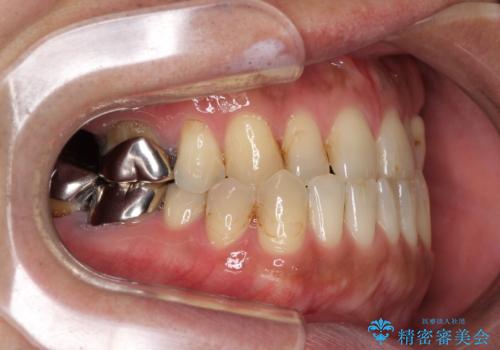

来院当初は、奥歯の銀歯が問題で咬み合わせが悪いと思っていらっしゃいましたが、前歯の反対咬合を改善することが最優先とご説明し、矯正治療を行うこととしました。

奥歯には抜歯が必要な歯があったため、事前に抜歯を行い、その後ワイヤー装置にて治療を開始しました。

今後はむし歯や銀歯を治療していく予定です。